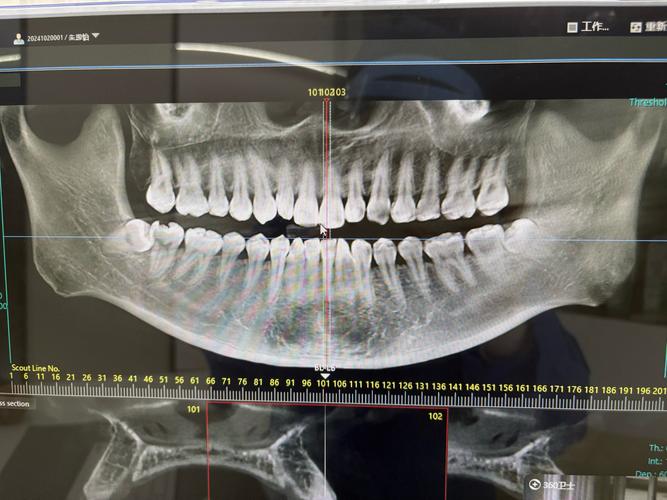

- 个体化调整:对于下颌中切牙存在修复体、严重龋坏或扭转的情况,需结合口腔内检查和CBCT三维影像辅助定位,避免单纯依赖二维影像的偏差。